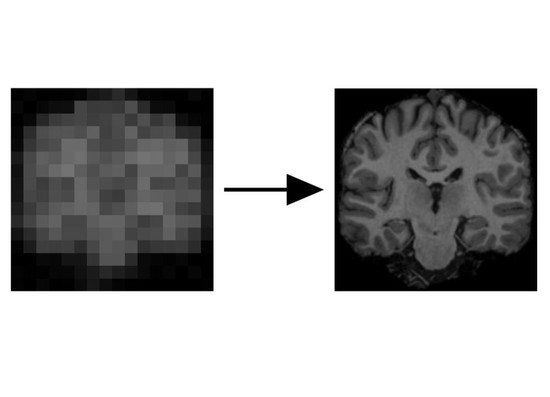

During my PostDoc in Polina Golland’s lab at MIT, I worked on machine learning algorithms for healthcare applications. I developed generative models for natural images, Chest X-Rays and brain images, which can be used as prior models for image reconstruction tasks, using bayesian posterior optimisation.

Using ML and compressed sensing techniques to improve the quality, speed and cost of medical scans.

Develop models for generation, reconstruction and manipulation of images, text or other high-dimensional data.